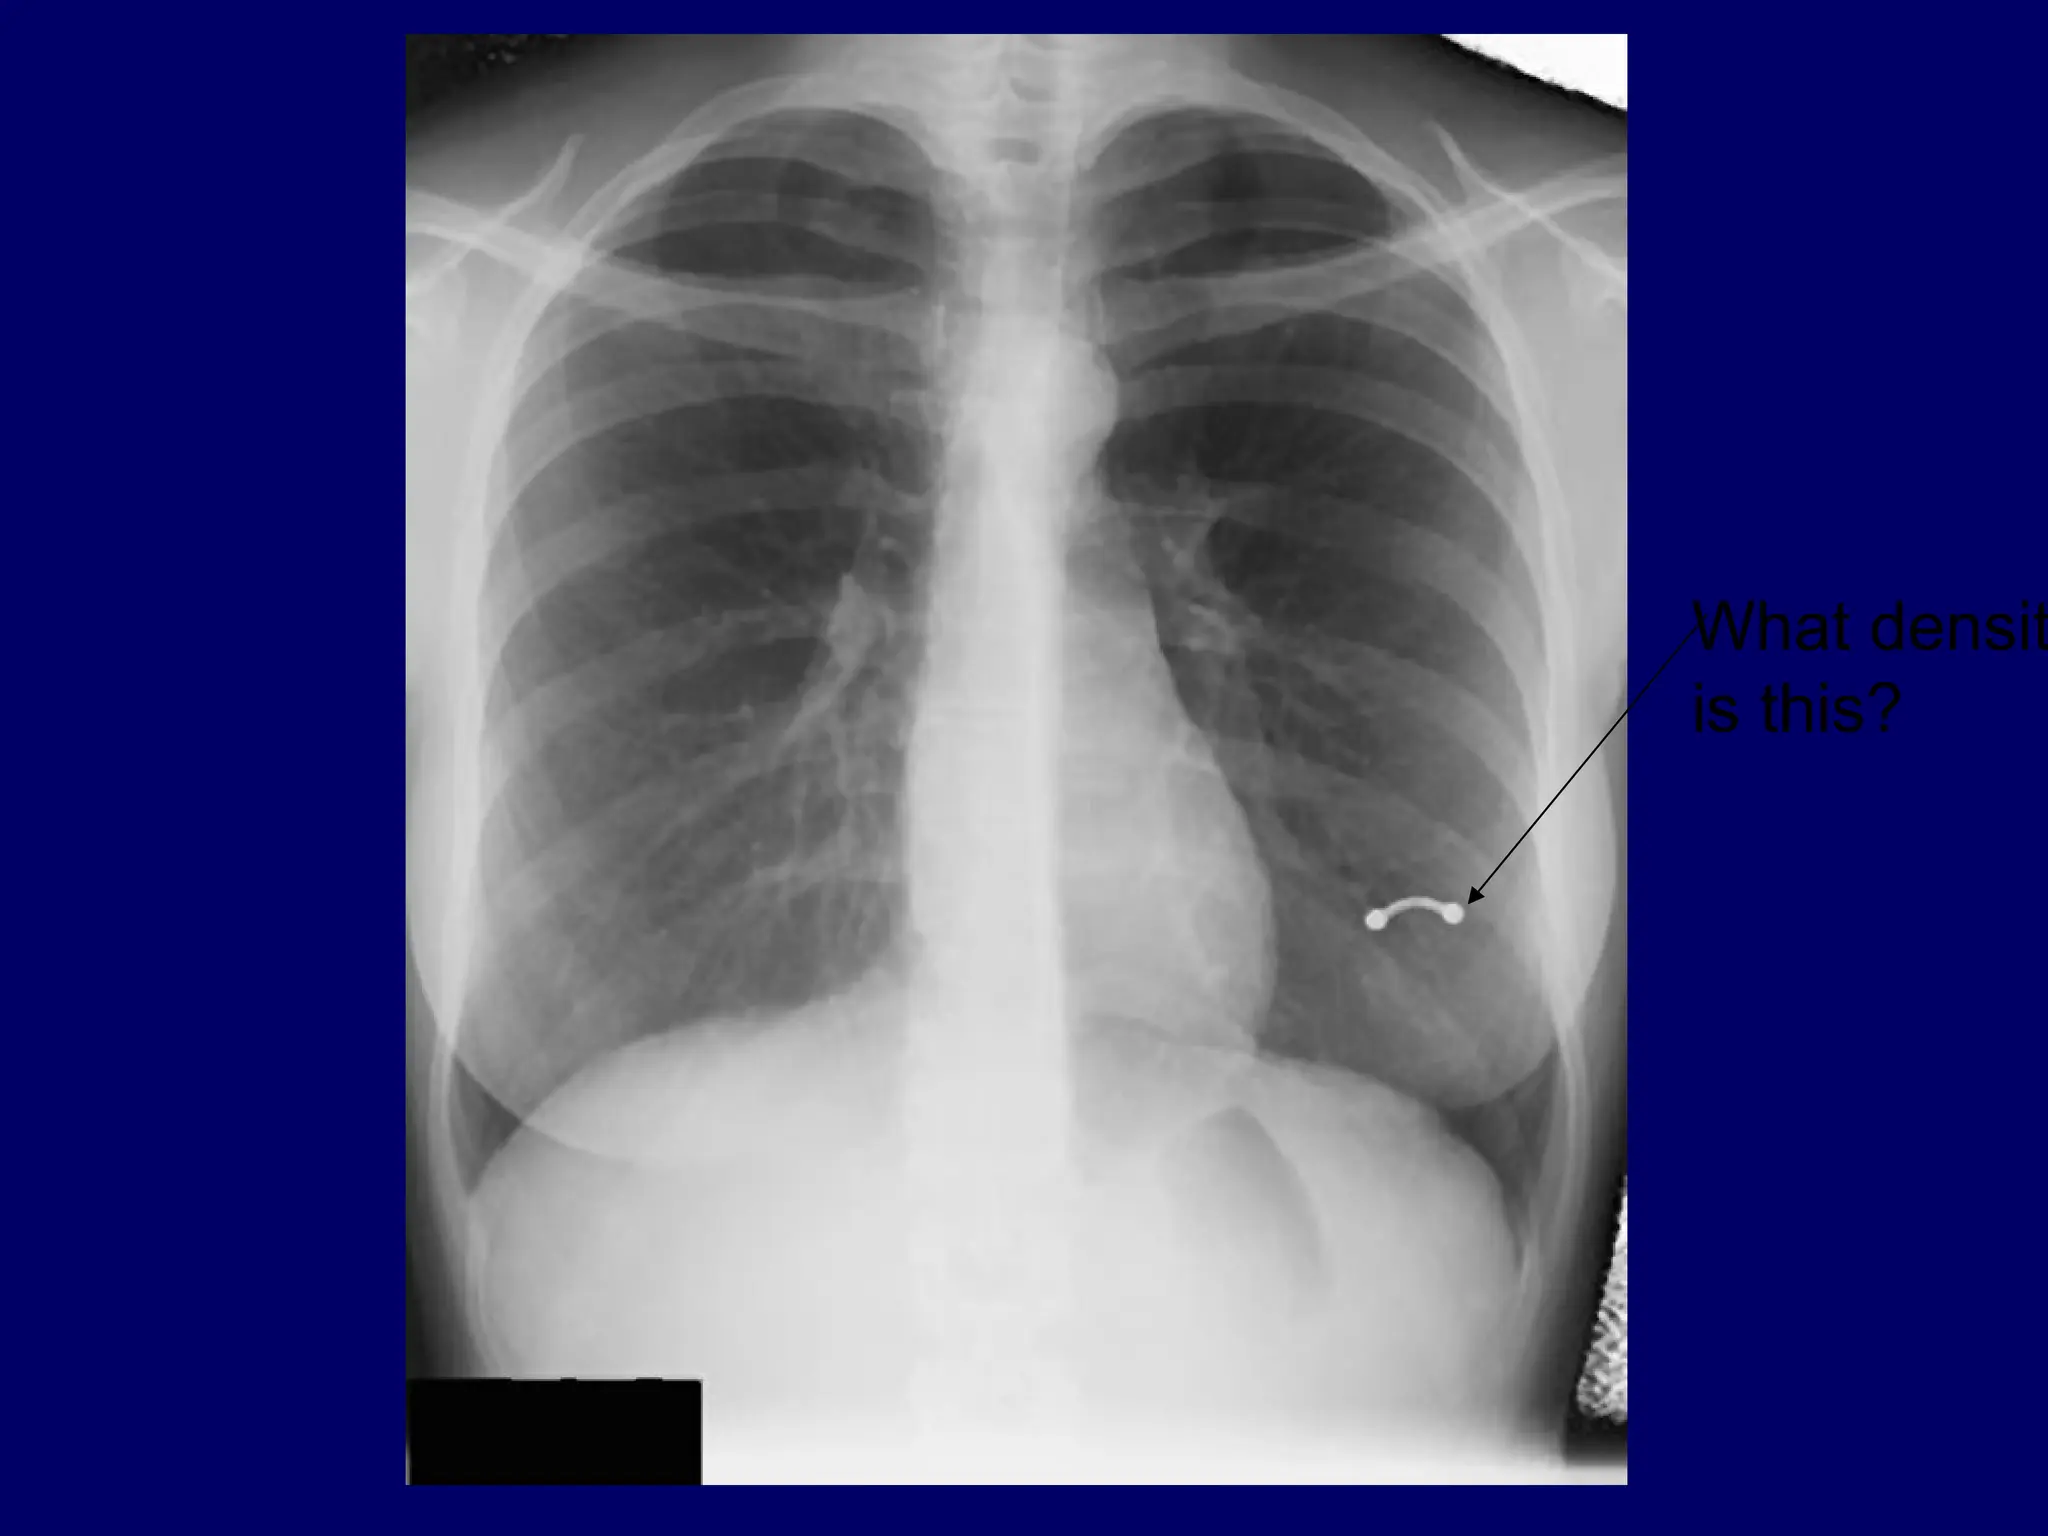

What density

are the

lungs?

Why?

What density is this?

A broken centralvenous catheter has migrated into the right lower lobe pulmonary artery